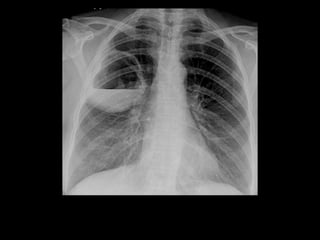

Radiological findings

o Airway obstruction

§ Atelectasis most common sign

§ No air bronchogram

§ Also post-obstructive pneumonia

o Hilar enlargement

§ From either the carcinoma itself or nodes

§ Particularly common in oat cell, uncommon in adenoca